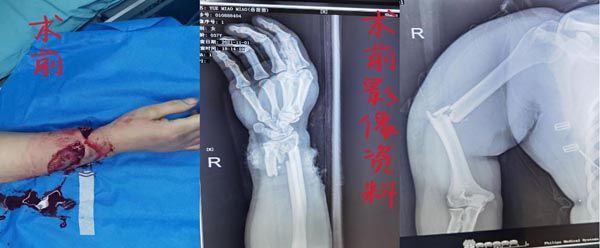

11月1日18时左右,陕西省核工业二一五医院咸阳骨科医院接收了一名浑身上下血淋淋的女性患者,经询问患者上班干活时被机器碰伤至头部、右腕、右上臂、左肩部及胸部,简单包扎后来院救治。值班医生曹雪飞紧急查体见患者右腕关节环形伤口,仅留下3cm皮条连接,伤口皮缘挫伤重,肌腱、骨折外露,右手缺血苍白,感觉、运动消失,伤口污染严重,右上臂及左肩部肿胀明显压痛阳性,头部皮肤深筋膜下撕脱等等。X片示:右尺桡骨远端骨折;右肱骨中段骨折、左肩胛骨粉碎性骨折,CT示右侧2-7、10肋骨骨折并胸腔积液,收住手·显微外科。

由于患者伤情严重,曹雪飞医生紧急联系蒋宏魁主任、医生周伟龙,组成诊疗小组,制定详细手术方案。为进一步缩短术前准备时间,治疗小组通知急诊手术室,协调麻醉师和手术护士,为急诊手术做好准备,同时进一步完善术前检查,联系配血及术后ICU。

20点患者被送往手术室,断肢再植不同于断指再植,要闯过很多难关,术中的麻醉风险、术中和术后的血管危象、大量输血的并发症等,此时距离患者受伤已经3小时了,在蒋主任的带领下,两位医生通力合作,克服种种困难,随着最后一针缝线的剪断,松止血带,末梢血运慢慢恢复,手指苍白转为红润,历时4小时的的手术圆满成功,所有人紧绷的神经才松了下来。然而这只是此次治疗的开始。断肢重建后的血运恢复,全身多处骨折的治疗,长期卧床的护理等一系列问题也随之而来。

11月11日配合胸外科行胸腔闭式引流术,11月12日联合骨二科全麻下行右腕清创缝合、左肩胛骨骨折切开复位内固定术,11月26日全麻下行右肱骨外固定架拆除、绕神经探查骨折复位内固定异体骨植骨术。经过多科室多次合作手术治疗及护理团队的悉心护理,目前患者病情平稳,右手末梢血运良好,已经可以自行下床活动。